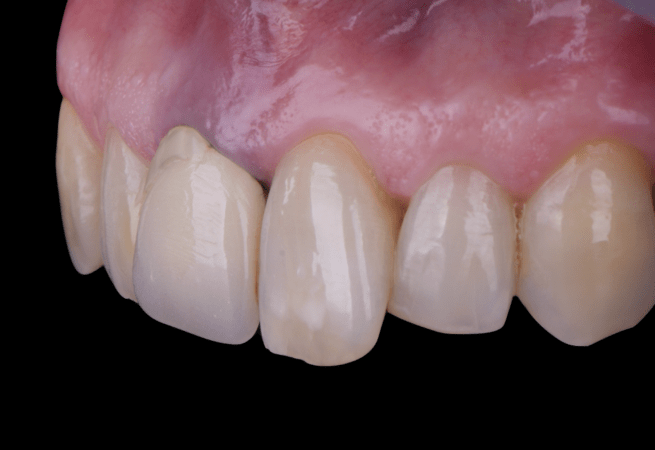

After an appropriate healing period, the definitive prosthesis was planned and delivered. A screw-retained zirconia crown was fabricated to ensure long-term durability, optimal esthetics, and retrievability. Zirconia was selected for its mechanical strength and excellent esthetic properties, blending seamlessly with the adjacent natural dentition in both form and color.

The final crown was designed to maintain the gingival architecture that had been shaped by the provisional. Special attention was paid to the emergence profile, contact points, and translucency to achieve harmony with the patient’s smile. The definitive restoration provided functional stability and esthetic integration, fulfilling the patient’s expectations for a fixed and natural solution.

This case demonstrates the benefits of combining immediate implant placement with simultaneous guided bone regeneration and connective tissue grafting in a high-esthetic area. The use of the N1 system and the “one abutment one time” protocol facilitated predictable healing and minimized disturbance of peri-implant tissues. Immediate provisionalization contributed significantly to soft tissue shaping and patient satisfaction throughout the process.

Key learnings include the importance of careful planning when treating cases with buccal bone wall resorption in the anterior maxilla. The integration of advanced biomaterials, such as creos™ xenogain™ and membranes, along with soft tissue augmentation techniques, ensures stability of both hard and soft tissues. This case reinforces that implant treatment in esthetic zones can achieve excellent outcomes when biological and prosthetic principles are applied in harmony.